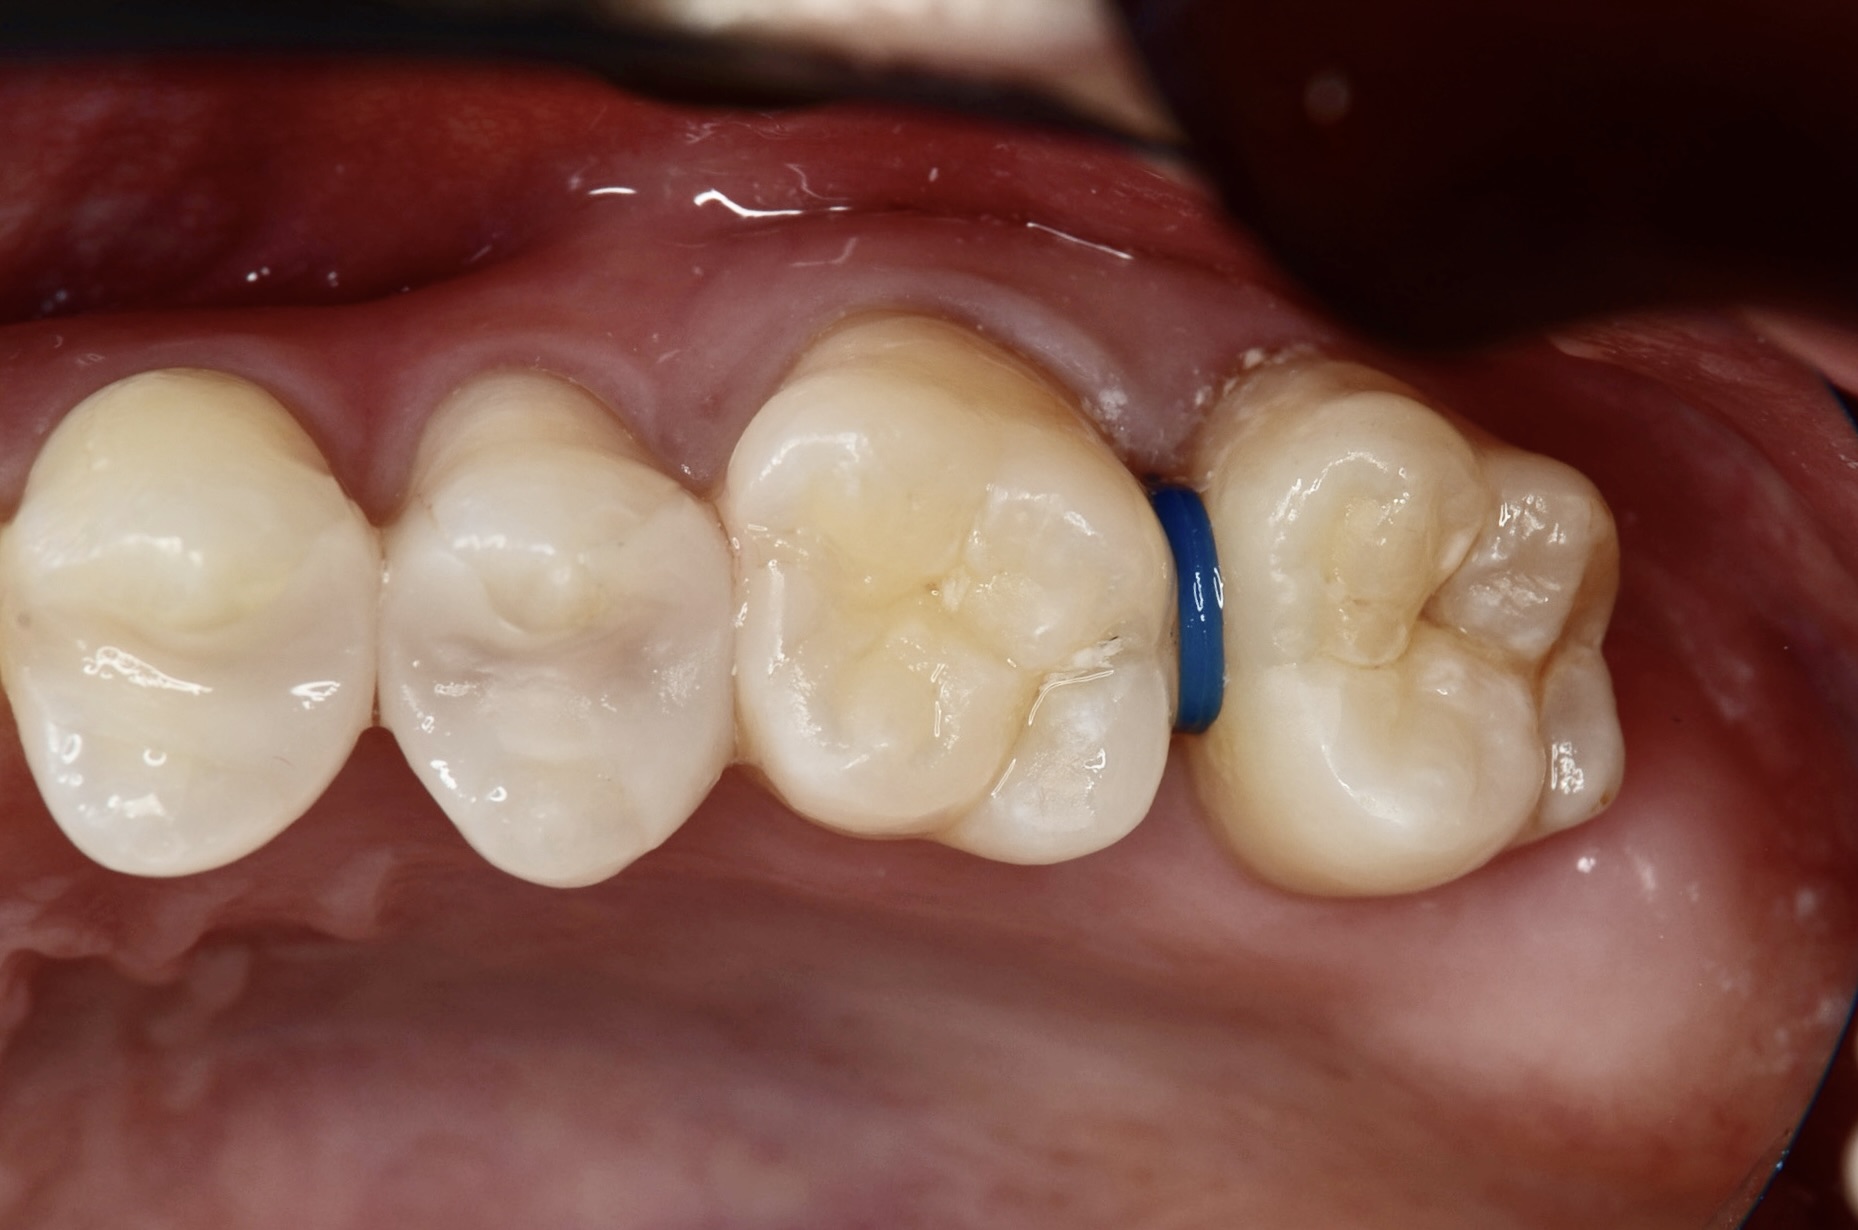

歯間離開用モジュールセット

歯間離開用の小さなゴムの輪をはの間に入れて1週間待ちます。 -

1週間後

ゴムの輪を外すと歯とはの間が少し開いています。 -